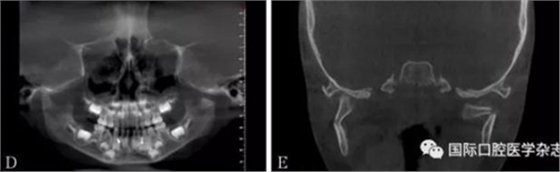

頜面部上下頜骨、顴骨及顴弓骨折、骨折片移位壓迫咀嚼肌群和下頜骨喙突,影響下頜骨的活動而造成張口受限[10-12](圖 9、10)。

A:患者面像;B:口內像;C:三維成像;D:全景片;E:冠狀位。

圖 9 面部外傷

左:顴弓骨折CT平掃;右:顴弓骨折CT三維成像。

圖 10 顴弓骨折